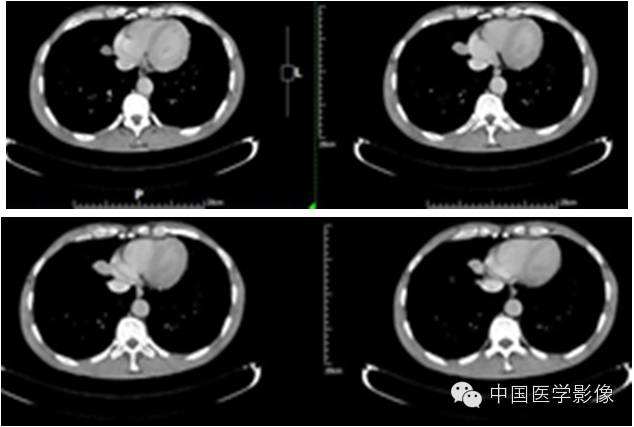

【影像资料】

平扫

动脉期

静脉期

延迟期